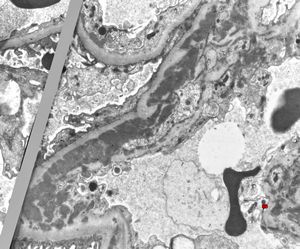

M,17y. | Alport syndrome - split and laminated basement membranes